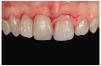

El pulido final es fundamental para el éxito estético de las restauraciones, ya que una superficie brillante y lisa reduce el acúmulo de placa y previene la decoloración de los dientes (Shiny System, Micerium). Al final, la restauración pulida presentaba una superficie muy similar a la del diente natural (figuras 49 y 50). No obstante, este nivel de resultado clínico obtenido con una técnica directa sólo es posible con un manejo correcto de la forma y la reconstrucción. Estos parámetros deben ser determinados antes de instaurar los procedimientos clínicos (figuras 51 y 52).

Figura 49 Vista de las restauraciones y los elementos rehidratados después de 72 horas.

Figura 50 Buena integración estética de las restauraciones y salud de los tejidos periodontales 30 días después del tratamiento.